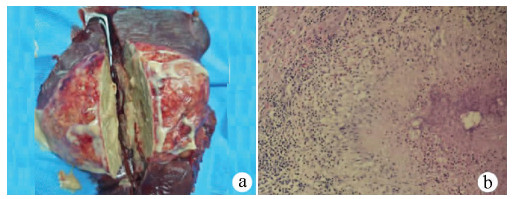

A case of hereditary hemochromatosis with diabetic ketoacidosis as the manifestation

Yingyue HU, Lisha LU, Zhenmao LI, Liangping LI, Lei LEI

2021, 37(5): 1177-1179. DOI: 10.3969/j.issn.1001-5256.2021.05.040

Abstract(1197) HTML (355) PDF (3389KB)(66)

Abstract: